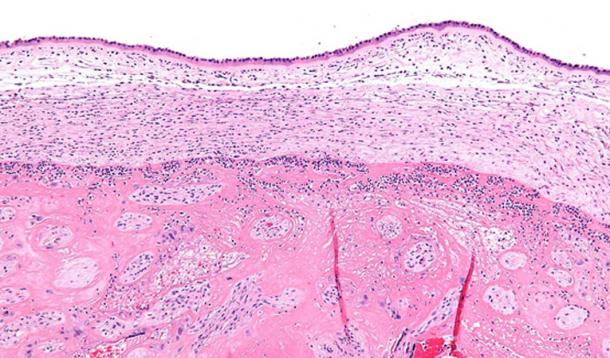

A cross section (measured in centimeters) of a calcified nodule found in a skeleton dating to Byzantine Troy, sometime around the 13th century. Cracking open the nodule, researchers discovered extraordinarily well preserved microfossils — mineralized ‘ghost cells’ — that closely resembled bacteria from the genus Staphylococcus, a family that includes many pathogenic species. The ghost cells yielded enough DNA for researchers to fully reconstruct their genomes. PHOTO: PATHOLOGIE NORDHESSEN

High magnification micrograph chorioamnionitis. (CC BY-SA 3.0)